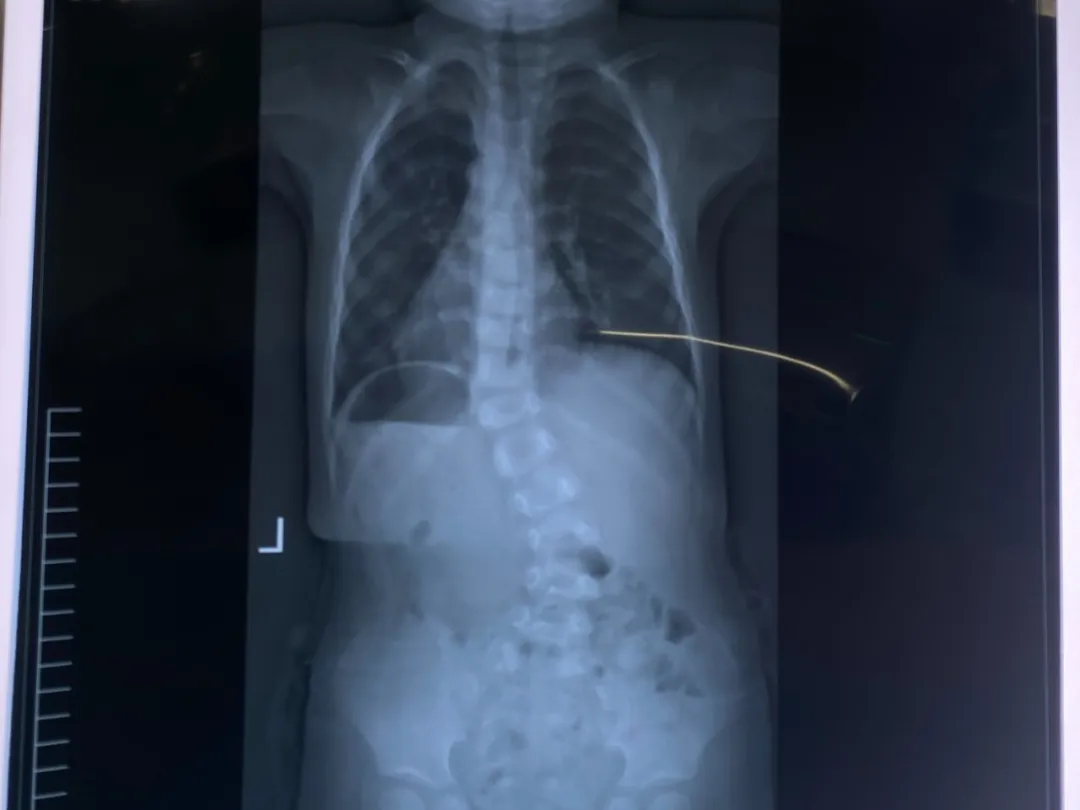

术中即刻的矫正效果

接诊后,高荣轩教授团队针对小迈的病情进行了详细讨论,为其制定了个体化治疗方案。鉴于孩子年龄小、侧弯角度大且伴有间断腰背部疼痛,决定给予分期石膏矫形固定,并专门准备了专业石膏牵引床。在北京儿童医院高荣轩教授的带领下,骨一科及手术麻醉团队紧密协作,顺利为小迈完成了Mehta系列石膏治疗。术后即刻透视显示矫形效果令人满意,侧弯角度得到有效纠正。整个手术过程顺利,仅用时30分钟,且为完全无创操作。术后小迈返回病房,家属也十分感激。